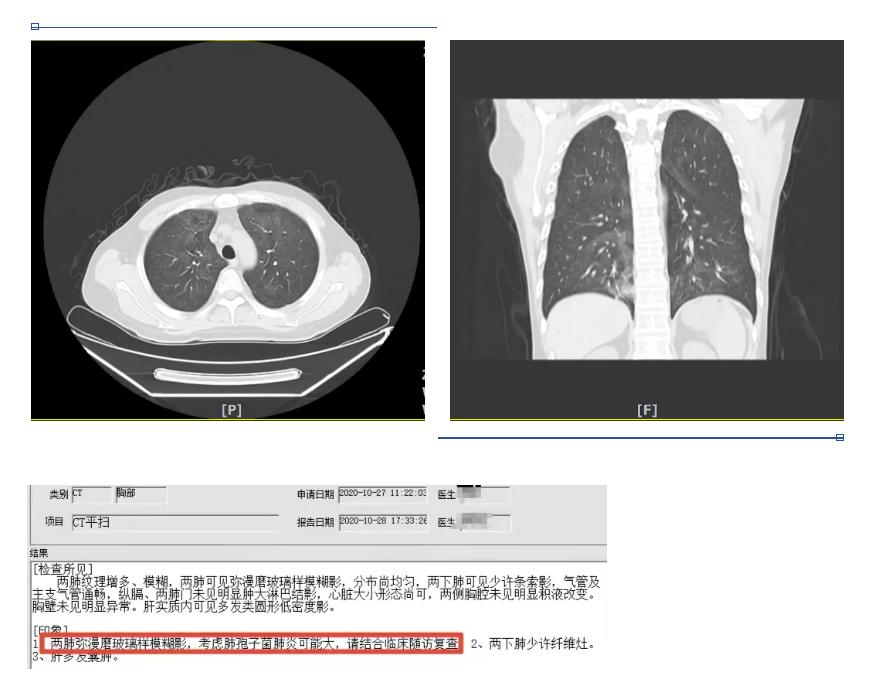

2020年10月27日因“淋巴瘤化疗后发热5天”来我院治疗。入院时血常规正常,CRP51.75mg/L↑,PCT阴性,血气未见明显异常,血清(1-3)-β-D-萄聚糖阳性(G试验)549.14pg/ml↑(≥100pg/ml阳性),GM试验阴性,LDH 537.3U/L↑、CMV和EB病毒定量阴性;胸片示肺间质改变明显,胸部CT示两肺弥漫磨玻璃样模糊影,考虑PCP可能大。

PCP影像学随着病程进展呈现动态变化,疾病不同时期表现可明显不同,典型表现为双肺弥漫性或局限性磨玻璃样影像,星云雾状、树枝挂霜样改变,呈非对称性、非均匀性随机分布;慢性或复发病例可引起间质结构和小叶间隔的增厚。